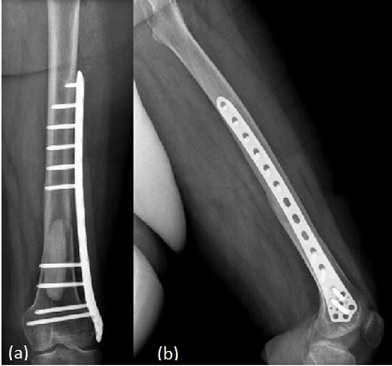

The overarching aim in the surgical fixation of geriatric DFFs is to achieve a stable construct that permits early weight bearing. Early mobilisation correlates to better survival, complications and discharge destination. Construct selection should therefore be individualised to fracture pattern (AO/OTA), bone stock, pre-injury function and surgeon expertise. Locking plates remain a versatile option for intra-articular, metaphyseal comminution and periprosthetic patterns, and can be delivered through minimally invasive techniques (Figure 1). Reported union rates are high, though failures cluster with suboptimal bridge-plating technique and certain implant orientations can irritate soft tissues [17]. Locking technology is particularly useful in poor bone quality as it bypasses the weak bone-plate contact and reduces vascular disruption and so use in geriatric populations is numerous.

Radiograph of a left distal femoral plate fixation. (a) - Anterior View. (b) - Lateral View Figure 1: Radiograph of a left distal femoral plate fixation. (a) - Anterior View. (b) - Lateral View [18].